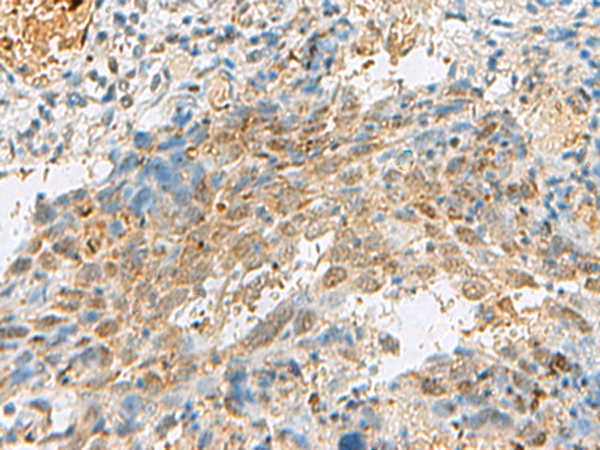

IHC (Immunohiostchemistry)

(Immunohistochemistry of paraffin-embedded Human cervical cancer tissue using PRPF3 Polyclonal Antibody at dilution of 1:30(×200))